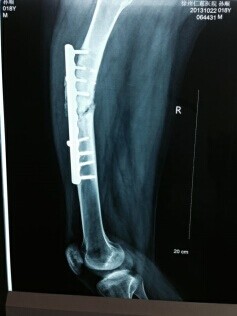

病例二:患者孙X,男,18岁,一年半前因外伤致右股骨骨折于外院行“右股骨骨折切开复位钢板内固定术”,术后复查骨折一直未愈合,四月前复查X片示右股骨内固定螺钉断裂。来我院检查以“右股骨术后骨不连 右股骨内固定螺钉断裂”收住入院(图一),于2013年10月26日在全麻下行“右股骨内固定取出+环形架外固定术”。术后患者可以带架行走,2014年02月22日复查已见骨折线模糊,骨痂生长连续。已经达到临床愈合标准(图二)。

图一 图二